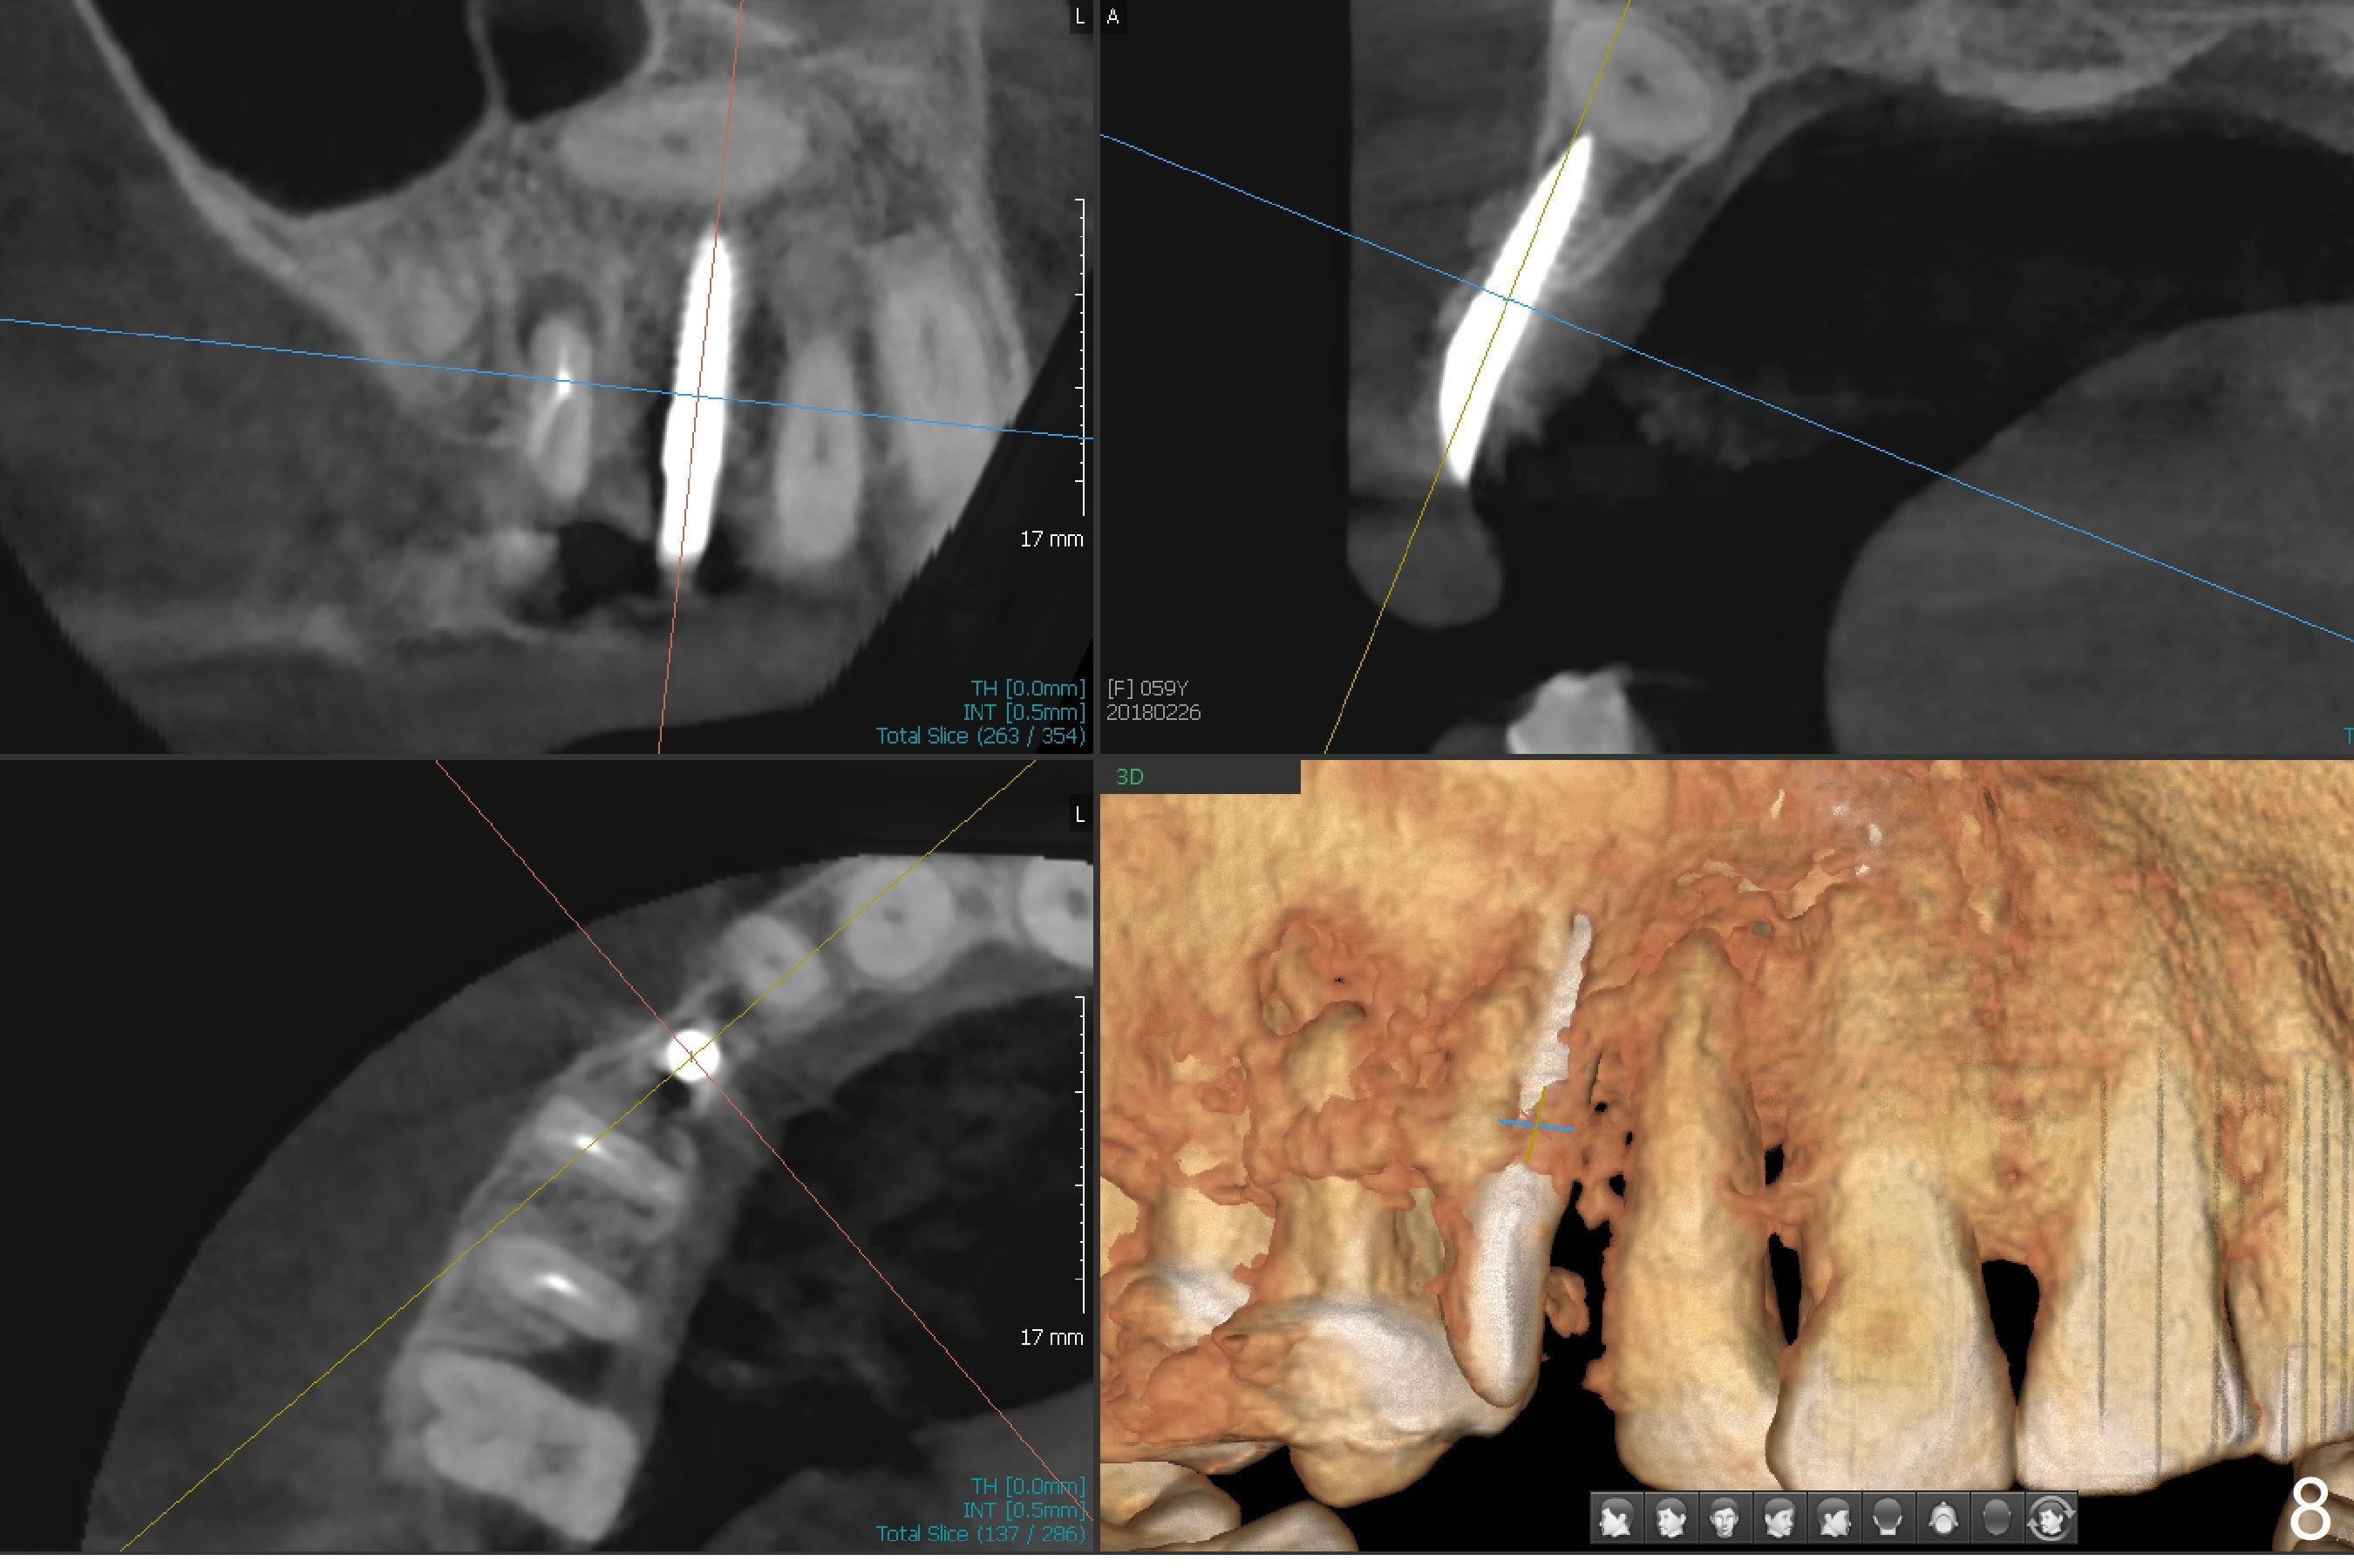

After removal the pontic of a cantilever FPD (Fig.1), a residual root is found at #6 with the buccal concavity (Fig.2 *). The ridge is narrow with flap elevation (Fig.3). PA taken with a 1.2 mm drill for 14 mm shows a horizontally impacted canine (Fig.4: #6). When the osteotomy is finished without apparently buccal perforation (Fig.5), the trajectory is buccal. When a 3x14 mm (12.5 mm in bone) 15 degree angled 1-piece implant is placed with normal trajectory (Fig.6), the buccal plate is perforated. As the implant is redirected so that the apical end of the implant does not stick out buccally, the trajectory returns buccal (Fig.7). The buccal aspect of the abutment is heavily reduced for an immediate provisional. The perforation is repaired with Vanilla Graft and Collagen Dressing before suturing. CT should have been taken preoperatively; the osteotomy should have been initiated as palatal as possible, as compared to that in Fig.5. When the 1st drill is used. it should be checked for restoration. An angled abutment does not help the trajectory substantially. The implant is loose 1.5 months (partially due to mastication); after retightening, CT is taken (Fig.8). The implant is within the bone. If the implant becomes loose again, extract the impacted canine and place the longest implant (22 mm) palatally. The implant is stable nearly 4.5 months postop (Fig.9). The patient is not satisfied with buccally-placed crown. The implant is removed with bone graft 6 months postop.